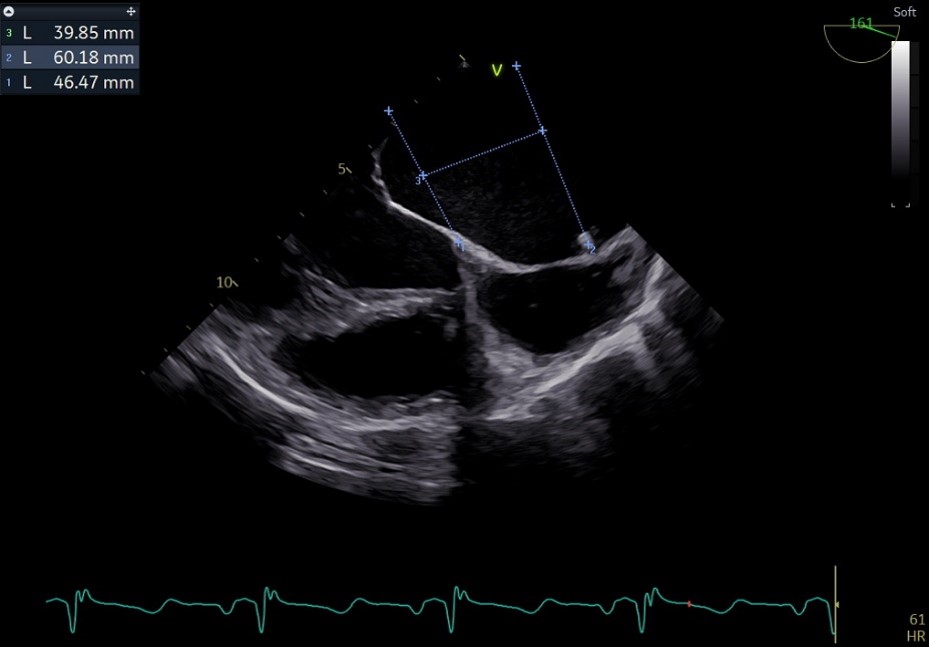

术前心超团队王蓓教授以及余婵教授对患者的瓣膜解剖情况进行了详细的评估:

① 二尖瓣后叶广泛栓系,前后叶对合不良,二尖瓣重度关闭不全,Carpentier分型Ⅲb,反流程度4+;

② 画迹法显示二尖瓣瓣口面积5.25cm²,平均跨瓣压差4.2mmHg;

③ 二尖瓣前叶(A1)长度28.5mm,二尖瓣后叶(P1)长度: 10.4mm;二尖瓣前叶(A2)长度28.4mm,二尖瓣后叶(P2)长度: 12.7mm二尖瓣前叶(A3)长度22.6mm,二尖瓣后叶(P3)长度: 11.5mm;

④ 3区前后叶对合gap 4.5mm,2区前后叶对合gap 3mm。

术前TTE